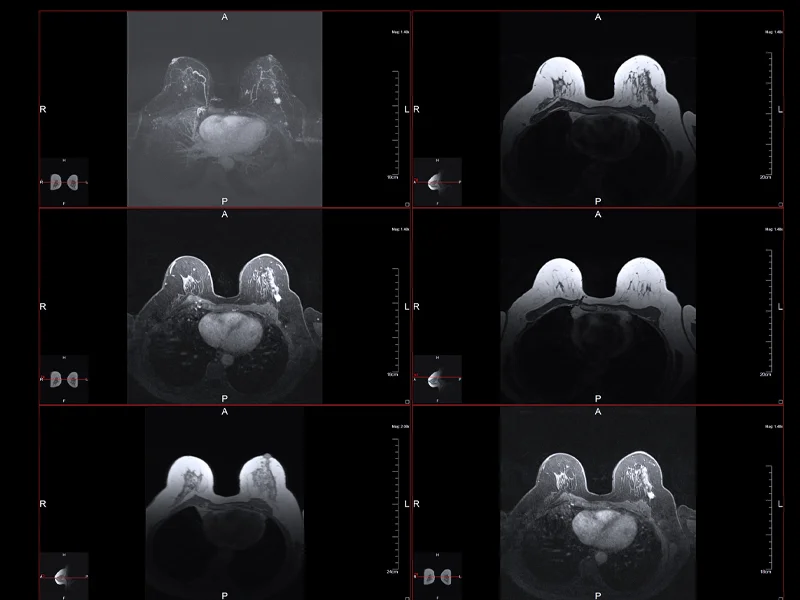

Breast cancer is diagnosed through various methods, including mammograms, ultrasounds, biopsies, and imaging tests. Treatment options depend on the stage of the cancer, its type, and the individual’s overall health. Common treatments include: